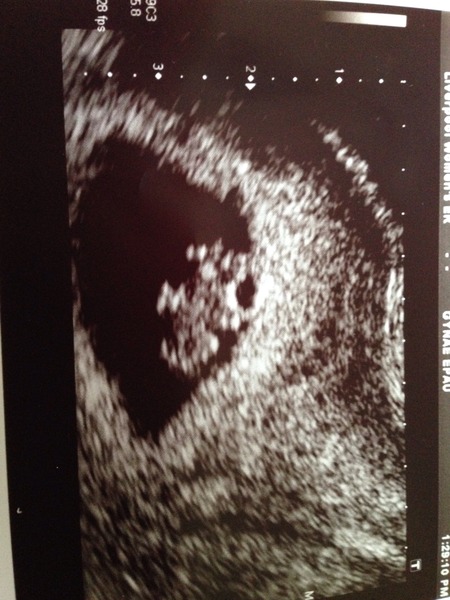

Well... Had an exciting day yesterday as had an early scan (due to 3 failed IVFs and 3 previous early miscarriages). I was really nervous beforehand thinking that there would be nothing there, it would be ectopic, it would be twins or even more! Thankfully all was perfect. I'm a couple of days further along than I thought- which makes sense re timing of sex as I was actually trying to avoid getting pregnant as I have a London Marathon place (deferred until next year now). So I am 8 weeks 1 day today. My little baby looked like one of those Pom Bear crisps with little arms and feet and a lovely beating heart. Measuring 15.9 mm. All looks perfect. I have a corpus Luteum cyst on my right ovary (which the consultant said was nothing to worry about and a good sign) which explains some niggling pains I've been getting.

Have attached a copy of my scan photo- not that I've ever been interested in anyone else's because they all look alien to me! But I thought people going for an early scan may be curious about what it may look like- I was expecting more of a blob than a little teddy bear!